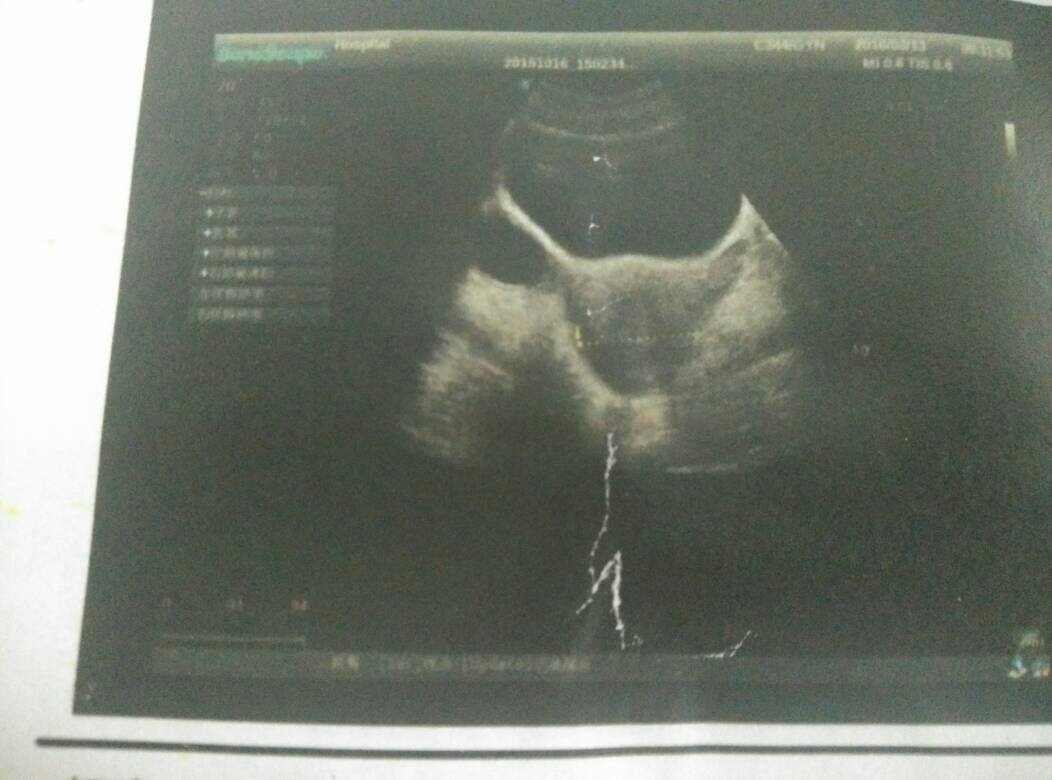

有妇科大夫么?帮我看看,我好几个月没正常来事了,都是吃药才来的。之前做彩超说没怀孕,但是子宫内膜0.45,开的黄体酮,吃完来事了,但是非常少,然后来事没走我就去医院了,做的彩超,那这个宫腔内的是什么,五个月没有性生活了。

检查结果显示:如果你确定5个月没有性生活,宫内的‘’无回声‘’考虑是妇科炎症;右侧卵巢囊肿;有盆腔积液。所蛇震以建议你详细咨俗怨残询医生,让医生给出建议积极配合治疗是厘趋很正确的。